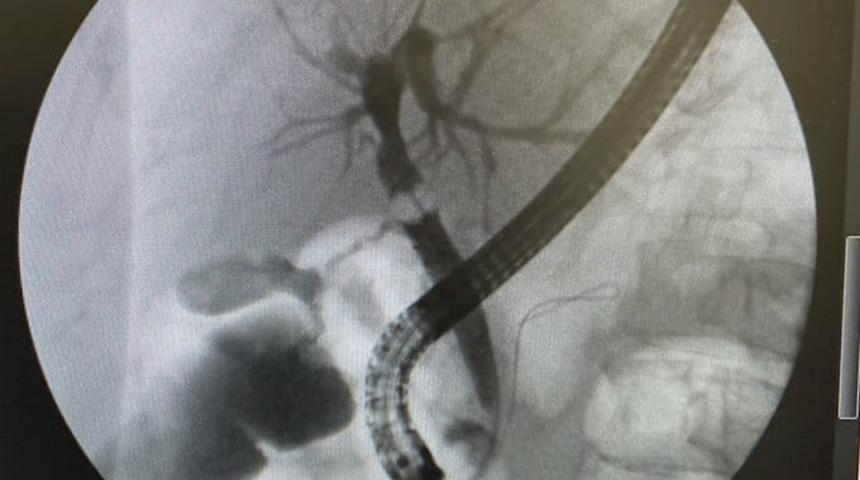

Ağrı’da yaşayan 84 yaşındaki S.S hasta karın ağrısı şikayeti ile hastaneye başvurdu. Yapılan tetkikler sonucunda safra yollarında ki taşa bağlı pankreas bezi hasarı tespit edildi. Hasta hastaneye yatırılarak tedavi altında alındı ve hastaya ERCP yapılarak safra yollarındaki taş endoskopik olarak çıkarıldı. İşlemi gerçekleştiren Gastroenteroloji Uzmanı Dr. Bayram Yeşil; " ERCP işlemi Türkiye’de belli merkezlerde yapılmaktadır. ERCP, Safra yolları, karaciğer ve pankreas bezinin bir takım hastalıklarında tanı ve tedavisinde kullanılan ileri gastroenterolojik işlemlerden biridir. Endoskopik olarak gerçekleştirilen bu işlemde, ameliyata gerek kalmadan hastanın safra yollarına girilerek işlemler yapılmakta ve safra yollarında ki taşlar temizlenmektedir. Safra yollarında taş bulunan hastamızın safra yollarını temizleyerek başarılı bir işlem gerçekleştirdik. Hastamızın servisteki takibi devam etmektedir. Şu anda bu işleme ihtiyacı olan 6 hastamızın servis takipleri devam etmektedir ve bu hastalarımızın da safra yollarında ki taşlar ERCP ile temizlenecektir. Daha önce bu hastalarımızı çevre illere sevk etmek zorunda kalıyorduk. Bugünden itibaren hastalarımızı sevk etmeden işlemlerini hastanemizde yapacağız. ERCP işlemi için teknik ihtiyaçlarımızın hızlıca tamamlanmasını ve bu işlemin hastanemizde yapılmasını sağlayan başta il sağlık müdürümüz Dr. Öğr. Üyesi Coşkun Daharlı’ya, başhekimimiz Opr. Dr. Cengiz Kazdal’a ve hastane yönetimimize teşekkür ederim” dedi.